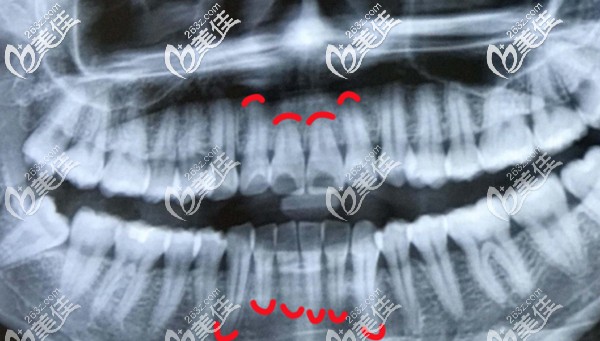

这张全景片的顾客,也是先天性牙根短,不过已经成功完成正畸了。不知道你的情况和她变比,差距大不,若比她的牙根还短许多,那就要慎重考虑是否要做矫正了,毕竟牙齿健康更重要嘛。